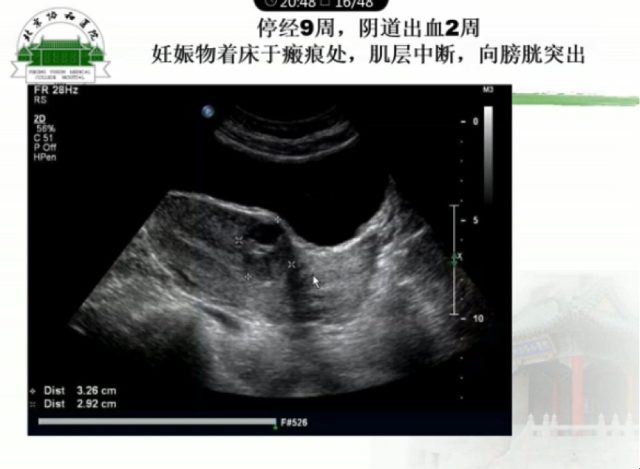

III 型:妊娠囊著床子宮前壁瘢痕處,向膀胱方向外凸;妊娠囊常明顯變形、拉長、下端成銳角;妊娠囊與膀胱間子宮肌層變薄,厚度<3 mm;彩色多普勒超聲顯示瘢痕處胎囊或包塊周圍見高速低阻血流,阻力指數一般為 0.4~0.5mJ。

CSP 首選經陰道彩色多普勒超聲結合經腹超聲進行診斷,診斷依據:

(1)子宮前壁瘢痕處見胎囊著床或不均質團塊;

(2)子宮宮腔及頸管處未見妊娠囊;

(3)前壁瘢痕處肌層連續性中斷,肌層變薄;

(4)彩色多普勒超聲顯示瘢痕處胎囊或包塊周圍見高速低阻血流,阻力指數一般為 0.4~0.5mJ。